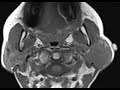

MALT Lymphoma

These images demonstrate asymmetric enlargement of the left parotid gland by a large infiltrative T1 isointense, T2 isointense, heterogeneously enhancing mass. The right parotid gland is somewhat heterogeneous in signal. In this patient with a history of Sjogren’s syndrome, the left parotid mass is most compatible with a parenchymal non-Hodgkins lymphoma such as MALT (mucosa associated lymphoid tissue) lymphoma which was confirmed on biopsy. Sjogren’s syndrome has a forty times increased incidence of MALT lymphoma. Treatment consists of radiation with possible chemotherapy.